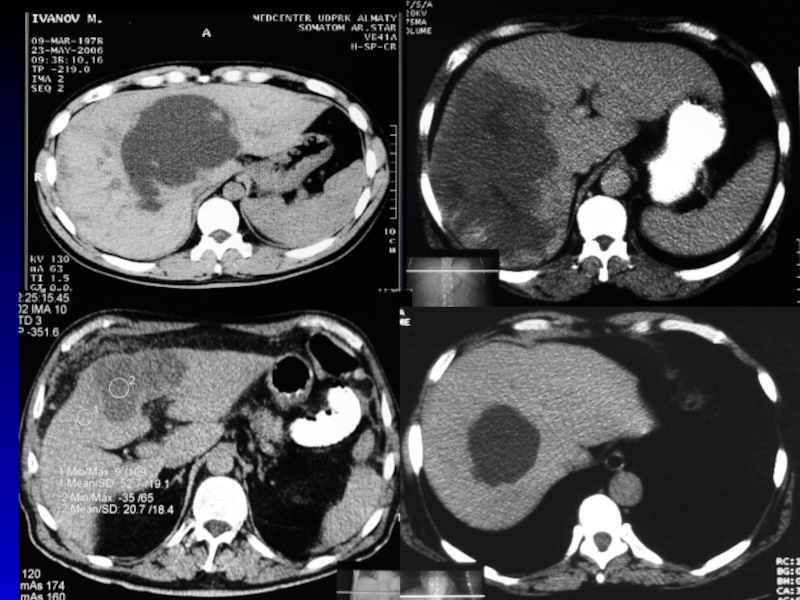

Слайд 22ДИАГНОСТИКА

Диагностическая пункция

УЗИ мягких тканей, рентгенологическое исследование , КТ,

радиоизотопное исследование.

ДИАГНОСТИКА Диагностическая пункция УЗИ мягких тканей, рентгенологическое исследование , КТ, радиоизотопное исследование.